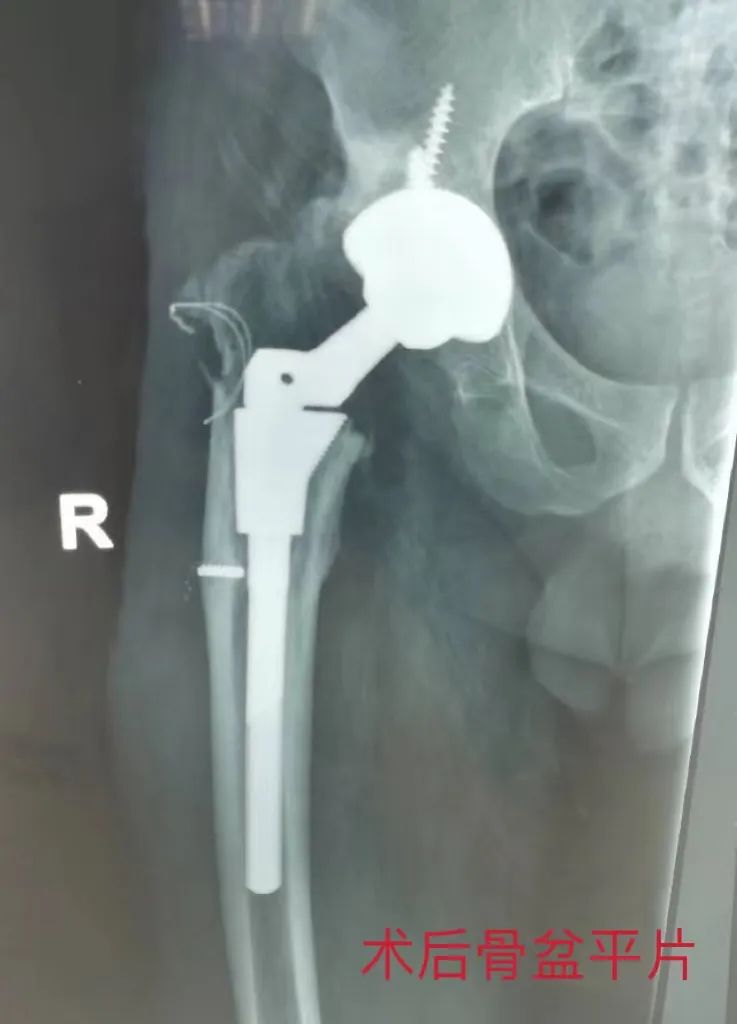

康某虽然年纪不大,但饱受髋关节疼痛30余年。30余年前行“右髋关节旋转截骨矫形术”治疗,初症状略有改善,随着病情发展,10年前右髋关节疼痛开始逐渐加重,并出现右髋关节内翻外旋畸形改变,患肢较健侧短缩近3cm,行走功能受限,长期顽固性疼痛,日常生活受到严重困扰。骨五科胡中申主任结合患者情况经过充分的术前评估后,在腰硬联合麻醉下给予患者实施“右侧股骨近端截骨组配式全髋关节置换术”,术后病人髋关节内翻外旋畸形得到矫正,髋关节疼痛明显缓解,术后第二天便可辅助行器行走锻炼,功能恢复满意。